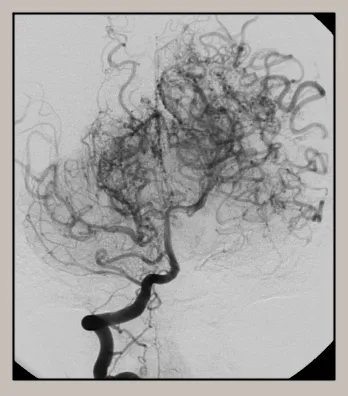

모야모야병(Moyamoya disease)은 특별한 원인 없이 뇌 속 특정 혈관, 주로 내경동맥 끝부분이 서서히 좁아지거나 막히는 만성 진행성 뇌혈관 질환입니다. 혈관이 좁아지면 뇌 혈류량이 감소하게 되고, 부족한 혈류량을 보충하기 위해 막힌 혈관 주변으로 가늘고 약한 비정상적인 미세혈관들이 자라나게 됩니다. 뇌혈관 조영술 이미지에서 이 미세혈관들이 마치 '연기가 모락모락 피어오르는 모양'과 같다고 하여 일본어로 '모야모야(もやもや)'라는 이름이 붙었습니다.

병태생리 측면에서 보면, 뇌혈관 협착에 대응하여 생성된 미세 혈관망이 특징적인 '연기 모양'을 나타냅니다. 최근 "기계-생물학적 이론(Mechano-biological theory)"은 혈관 구조의 차이 등 여러 요인이 복합적으로 작용하여 광범위한 뇌혈관 폐색을 유발하고, 손상된 뇌에 혈액을 공급하기 위한 혈관 연결의 변화를 초래한다고 설명합니다. 일단 발병하면 혈관 폐색은 알려진 내과적 치료에도 불구하고 계속 진행되는 경향이 있습니다.

- 뇌혈관 조영술(Cerebral Angiogram): 가장 정확한 진단 방법 중 하나입니다. 사타구니 혈관을 통해 가느다란 도관(카테터)을 뇌 혈관까지 삽입한 후 조영제를 주입하고 X선 촬영을 하여 뇌 혈관의 협착 정도와 특징적인 모야모야 혈관을 직접 확인합니다.